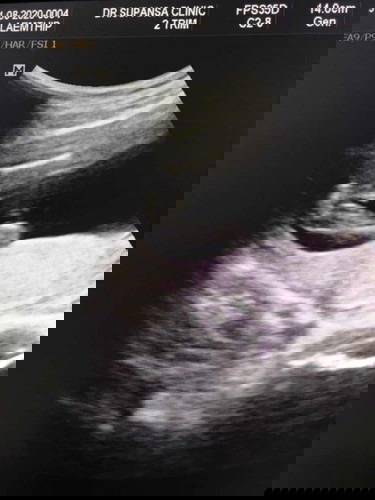

ผู้หญิงหรือผู้ชายคะ🤣

ใช่จู๋ไหมคะแม่ๆ หมอไม่ยอมคอนเฟิมให้ แต่แม่คิดคิดว่าน่าจะเป็นจู๋🤣 แม่ๆคนอื่นคิดว่าไงคะ

มาเป็นแท่งแบบนี้ชายค่ะแม่😂😂

คิดว่าใช่นะคะแม่ 😂😂